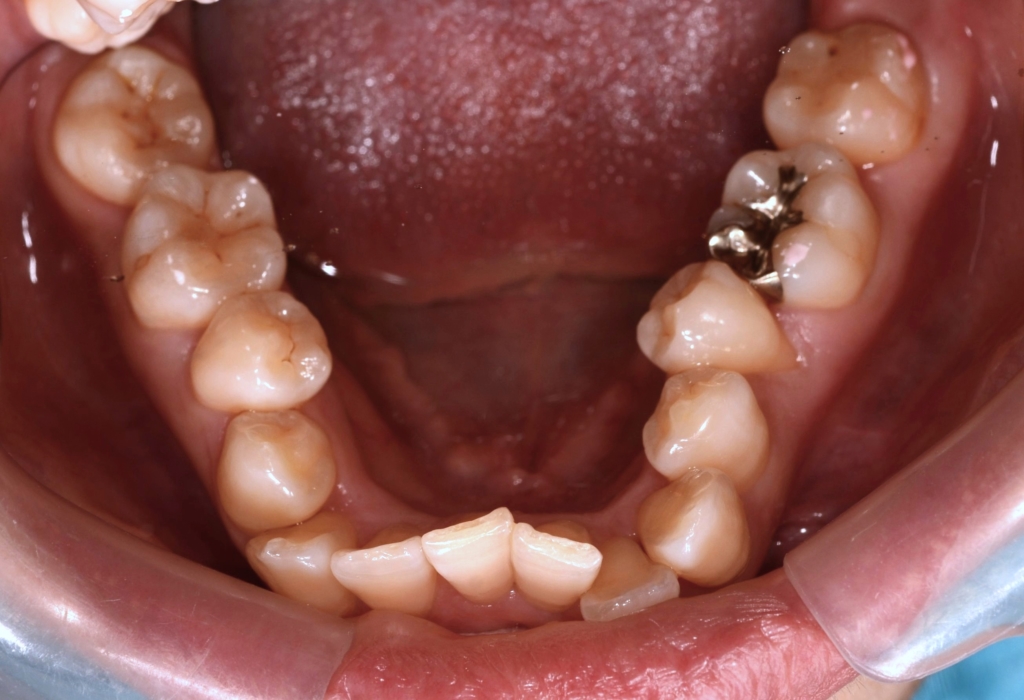

#1.顎と歯の不調和による叢生(重度)

#2.上顎前突(出っ歯)傾向

と診断しました。

1.上下の左右の奥歯を抜歯をしてスペースを作り、前歯をきれいに並べる

上下の左右の奥歯を1本ずつ計4本抜歯(4番目の奥歯を抜きました)

(左下奥の横になって埋っている智歯は様子見です)